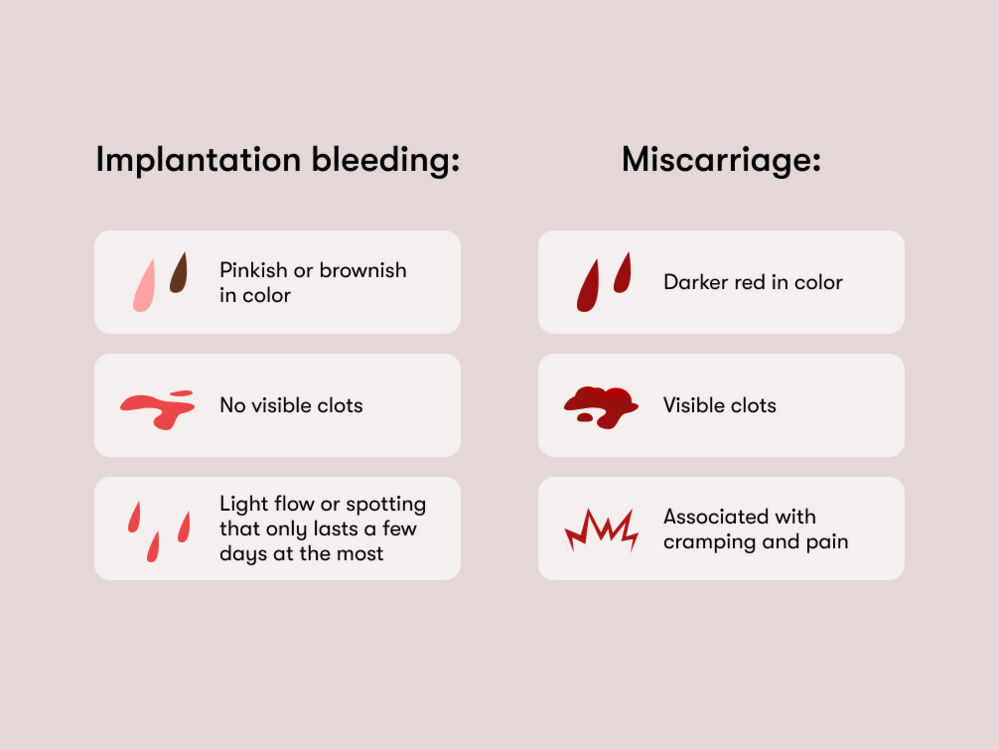

Spotting During Pregnancy

Early Pregnancy Bleeding And Progesterone Tommy s